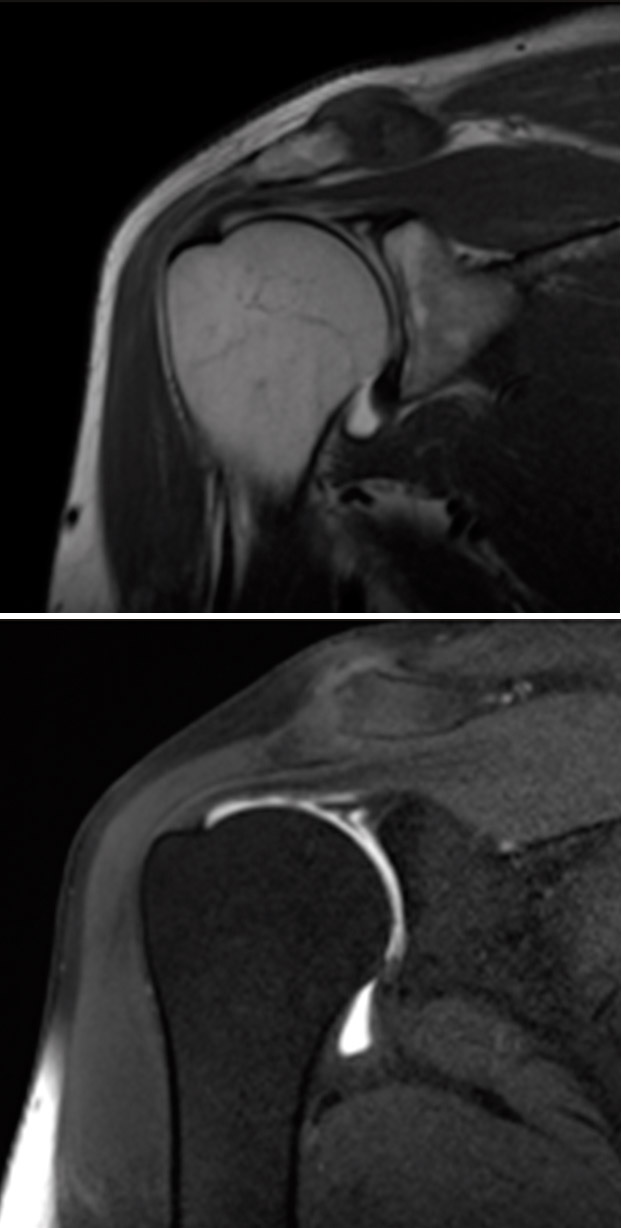

A la exploración física se evidenció movilidad completa, maniobras negativas para lesión de manguito de rotador o patología de articulación acromioclavicular. La exploración física fue positiva y compatible con lesión de SLAP (superior labrum anterior to posterior), confirmada con la artrorresonancia magnética (artro-RM) y diagnosticada como SLAP de tipo II; se programó para reparación artroscópica (Figura 1).